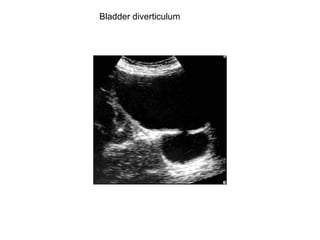

Bladder diverticulum

Calculus in a diverticulum